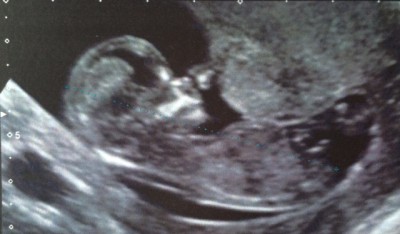

Merci pour vos petits mots ! Je n'ai pas passé une nuit terrible, et j'ai été excecrable ce matin. J'avais trop peur qu'on me dise "désolé, il s'est arreté de grandir, c'est mal barré, tout ça tout ça". Et bien ça sera pas pour cette fois, tout va bien ! Ouf ! Je pense que de toutes façons, je serai en stress pour n'importe quoi toute la grossesse. Prise de sang tri test faite, y a plus qu'à attendre. Clarté nucale à 1,4mm. et bb fait 6 cm !

Bébé a bougé de folie, c'est impressionnant de le voir se tourner dans tous les sens. J'ai pas vu ses jambes par contre mais mon mari et l'echographe me disent que oui et que pour le moment, il est tout a fait normal.

Bravo pomm elle est belle ton echo ! C'est parti pour le concret ;)

Au fait Pomm! Génial pour l'écho et très belle photo!!! Bonne idée la robe de grossesse! Je n'ai pas encore sauté le pas, moi j'ai commencé à tricoter pour le bébé par contre mais ça fait des années que j'en rêve!

Pomm très jolie photo ! Jonquille super nouvelles ! Félicitation !